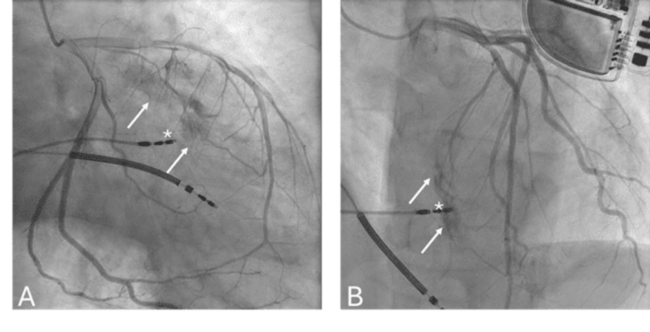

Coronary angiography (Figure) demonstrated contrast extravasation (Videos 1 and 2) from a large septal branch of the left anterior descending coronary artery toward the right ventricle. Given the small shunt and the asymptomatic presentation, a conservative management strategy was adopted.